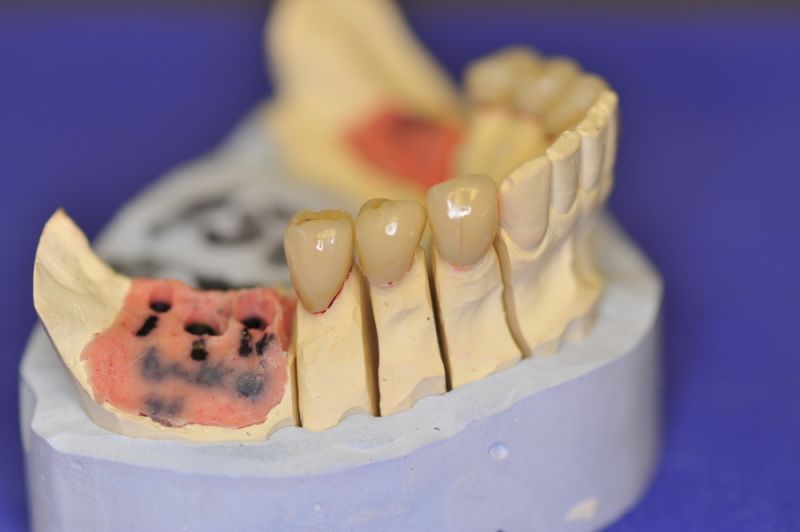

Mit dem heutigen Tag geht eine der technisch schwierigsten und anspruchsvollsten Arbeiten zu Ende, die im CMD-CENTRUM-KIEL jemals erstellt worden ist. Dabei sind es nur 10 Kronen, die benötigt werden, um die starken Kopf- und Gesichtsschmerzen der Patienten zu beseitigen.

4. Notwendigkeit die Mundhygienefähigkeit der Arbeit auch unter sehr beengten Verhältnissen zu schaffen, um der Arbeit eine günstige Prognose mitzugeben.